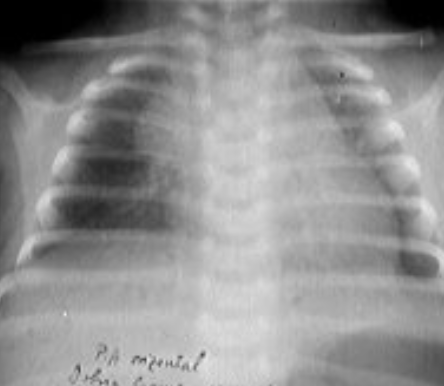

Rx toracică, incidență P-A

DESCRIERE:

DX: emfizem pulmonar

DD: